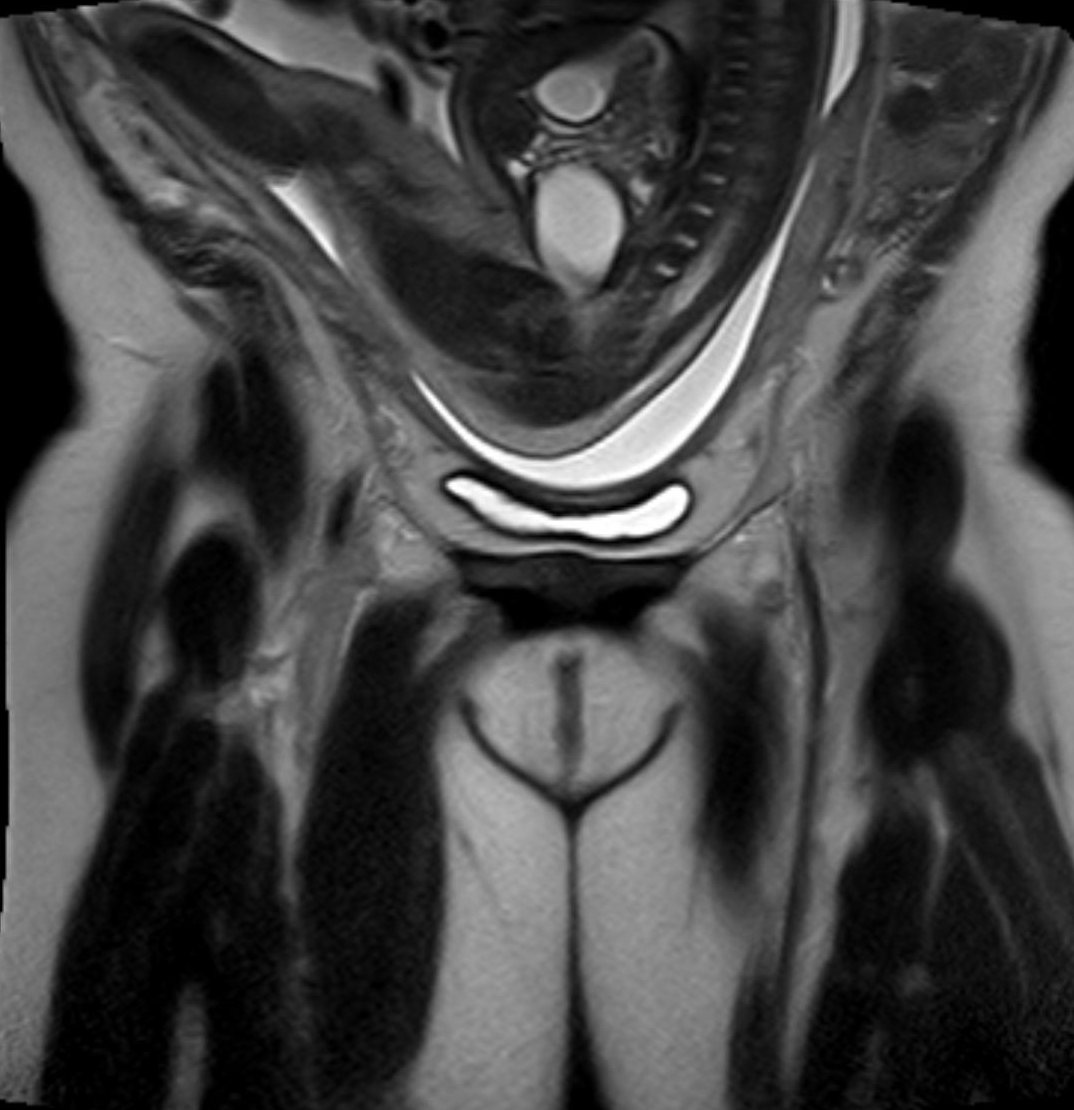

Wiki breech presentation picture This picture illustrates wiki breech presentation.

Breech presentation is a leading cause of cesarean delivery. Breech presentation is when the baby's bottom is down. Breech presentation is normal throughout pregnancy. Unstable lie - this is where the presentation of the fetus changes between transverse/oblique/breech and back. See breech presentation for additional information; transverse/oblique lie - often results in shoulder or arm presentation.